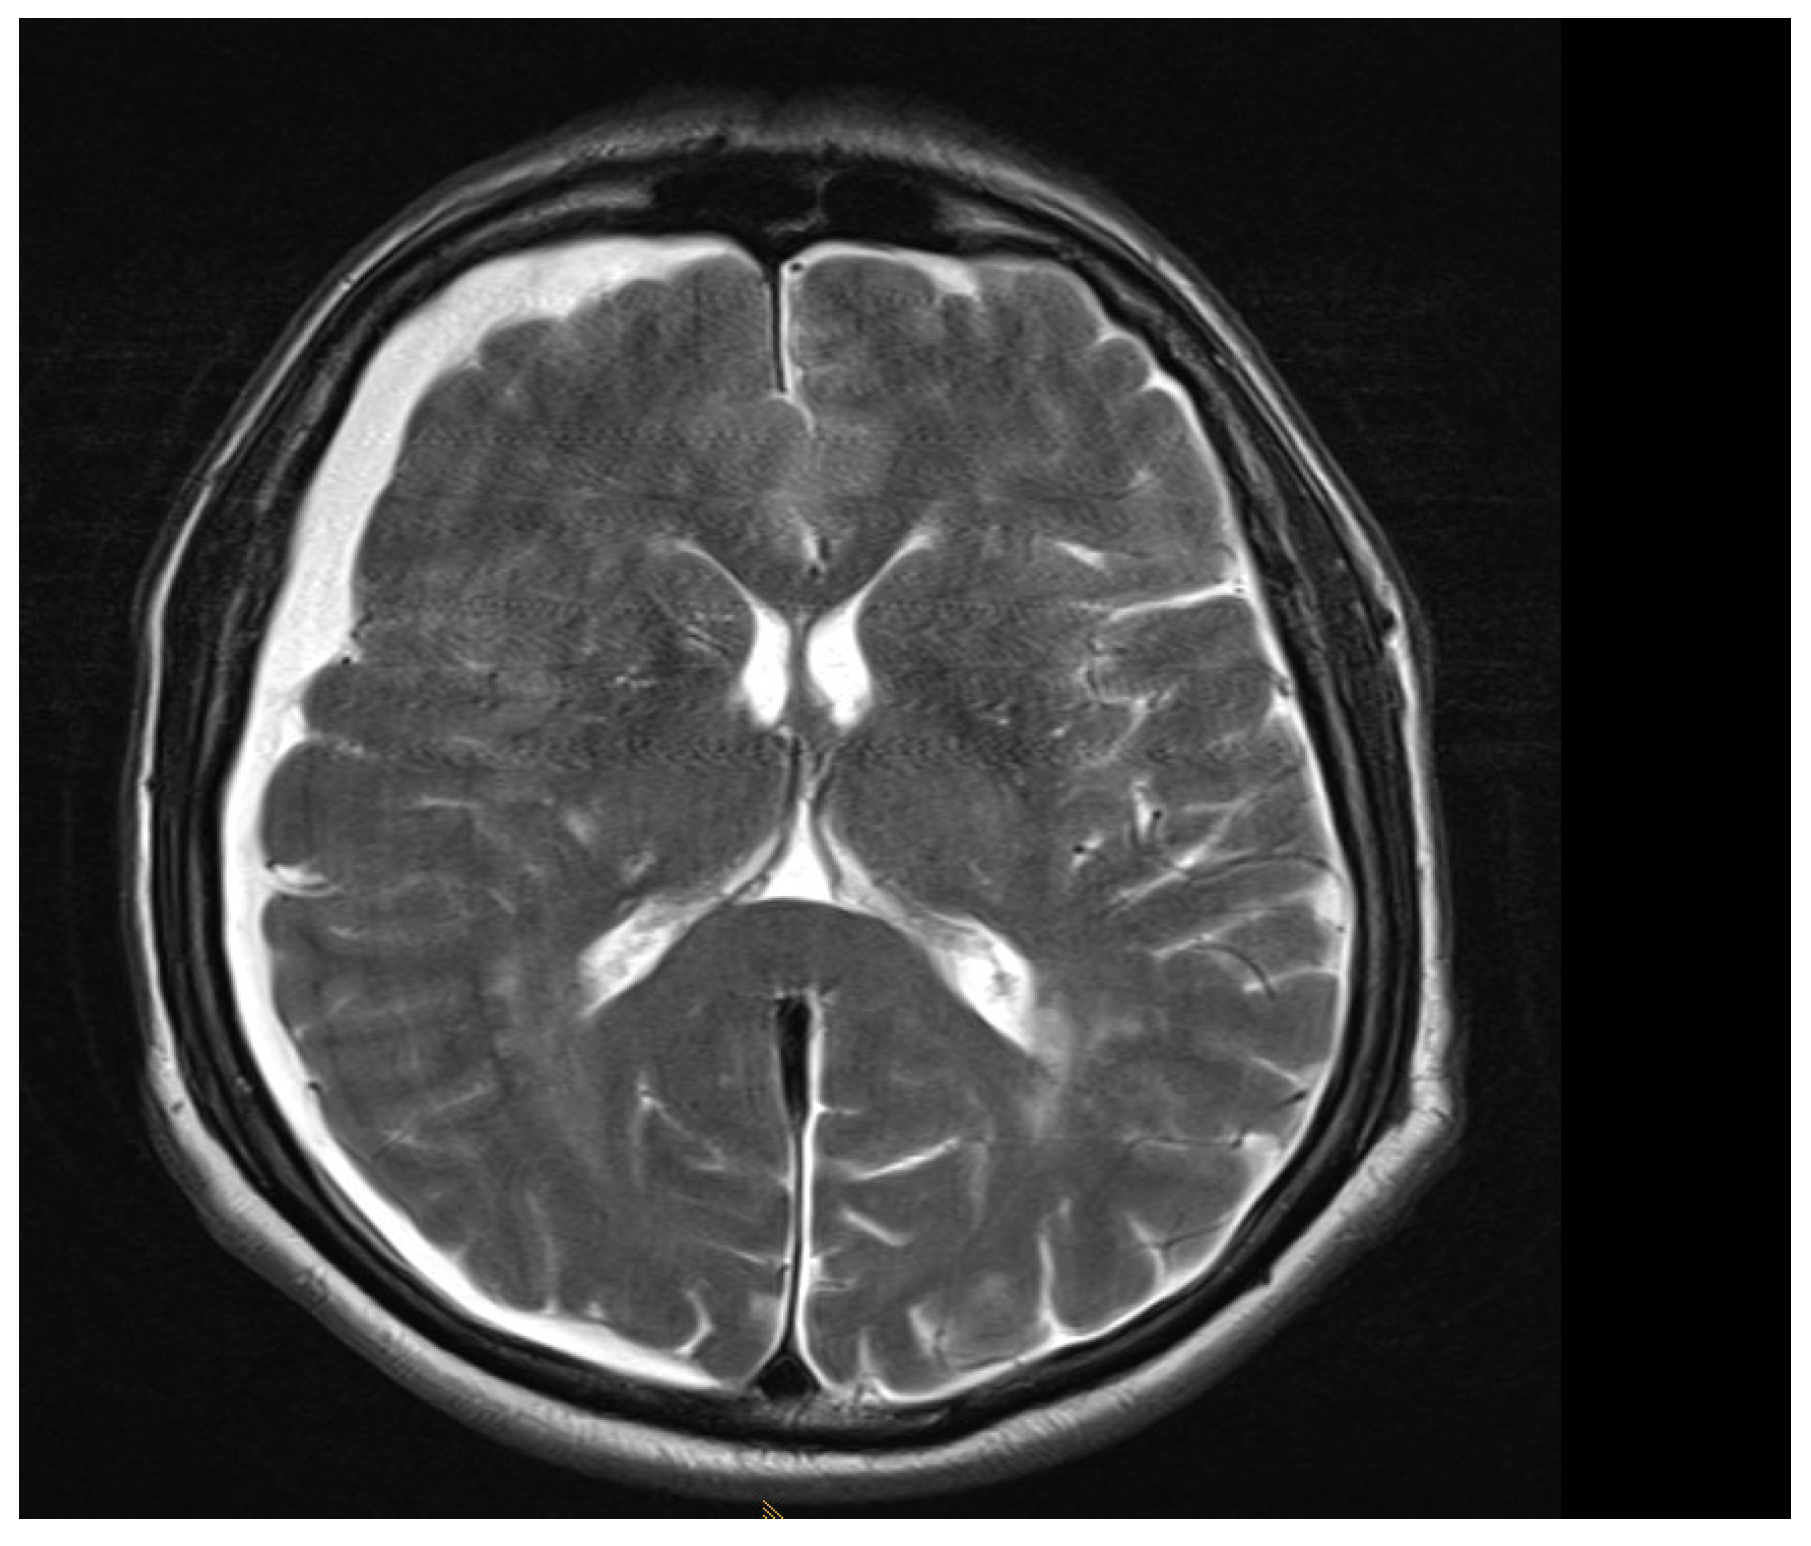

Among the 722 punctures, complications occurred in four cases (0.6%), see Table 3. Three of these complications arose after the first administration and one after the second. Reported complications included one case of post-puncture aggravation of pain, and one case of post-puncture headache. Both cases were managed conservatively using analgesics. In one case, shortness of breath occurred. In this patient, a cardiopulmonary event was ruled out, which required performing blood sampling as well as a CT-angiography of the pulmonary arteries. In another case, an intracranial subdural hygroma occurred, see Figure 2. No neurological deficits occurred, but due to persistent headache, an MRI scan was performed which revealed the diagnosis. The patient was readmitted for inpatient treatment for another 5 days 1 month after initial puncture. An MRI scan of the lumbar scan revealed epidural accumulations of cerebrospinal fluid at the thoracolumbar junction (Figure 3). Bed rest was ordered for 3 days. 2 days after readmission, a CT-guided lumbar blood patch was performed at the level L2 with 35 mL of blood, and oral analgesics were administered. The patient was discharged after five days. At subsequent follow-up visits, the patient reported no further headaches, and an MRI performed six weeks later demonstrated the complete resolution of the epidural cerebrospinal fluid collections (Figure 4).

Figure 4. Axial T2 weighted MRI at L1, 6 weeks after blood patch. No epidural cerebrospinal fluid collections can be distinguished anymore.